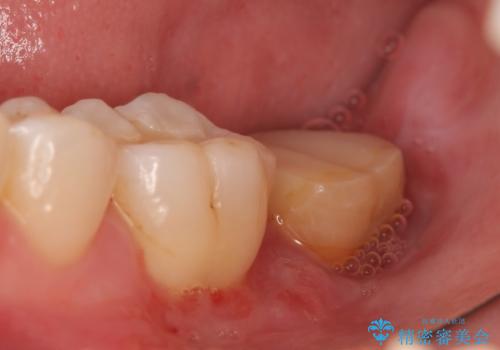

- 左下の一番奥の歯が時折激しく痛むので診て欲しいといらっしゃった方の症例です。以前に他院を受診したところ、そもそも被せ物を入れるスペースがないため抜歯しかないと言われたとのことでした。

診査の結果根尖病変を認めたため再根管治療を行った後に、被せ物を入れるスペースを作るため歯冠延長術を行いました。

歯冠延長術について

歯冠長延長術とは歯肉弁根尖側移動術とも言い、歯の高さが低くクラウン(被せ物)による治療が難しい場合に、歯茎を歯根方向に下げることで歯の高さを確保する手術です。歯の高さが十分にあることで、外れにくいしっかりとしたクラウンを被せることができます。